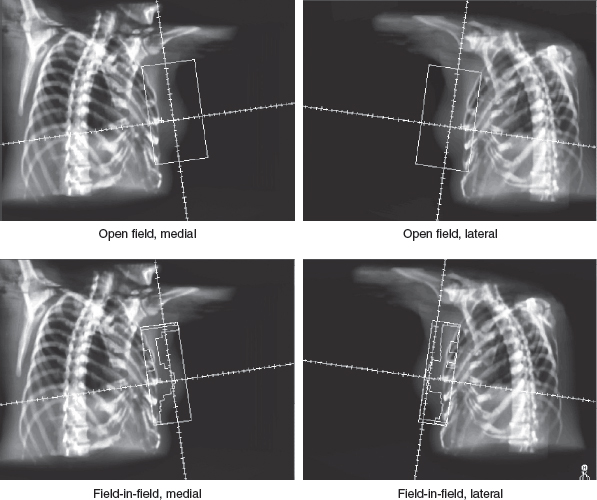

There are various compensation methods used to modulate the dose distribution to achieve improved homogeneity. One such technique is the open-field, uncompensated treatment plan (see Fig. 10-1). One technique that is widely used to ameliorate dose inhomogeneity is the placement of compensator devices in the beam, often using wedge compensators of fixed angles or, more recently, virtual wedges of variable compensation degrees. The wide part of the wedge (or compensator) is placed in the beam in the same orientation as the tip of the triangle of the breast, to compensate for the thinner tissue separation at the apex of the breast at the nipple area.

After multileaf collimation (MLC) became available, custom compensation using field-in-field MLC shaping became increasingly popular. With this technique, the MLC is used to shape smaller fields that correspond to the areas of high-dose inhomogeneity, covering the high-dose regions with custom-shaped fields for small portions of the total dose to improve homogeneity. Another technique, intensity-modulated radiotherapy, typically involves three-dimensional planning using dose-volume constraints for target tissues and normal organs, with either forward or inverse planned dose calculations. Each compensation method can reduce and redistribute the “hot spots” (isodose regions in excess of 100% of the prescribed dose) compared with open fields with no compensation.